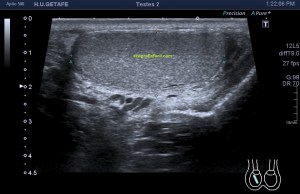

Al llegar al compartimento 6 me encuentro un tendón engrosado de tamaño y aspecto heterogéneo típico de afectación por tendinosis, con líquido en la vaina, te lo señala la imagen con flecha amarilla. Lo recorro y confirmo los hallazgos eje corto y eje largo, hago medidas y compruebo el doppler que marca Neovascularización asociada.

Observa las tres imágenes superiores, son muy ilustrativas, son comparativas de normalidad hallazgos patológicos, el izquierdo claramente patológico y el derecho claramente normal.